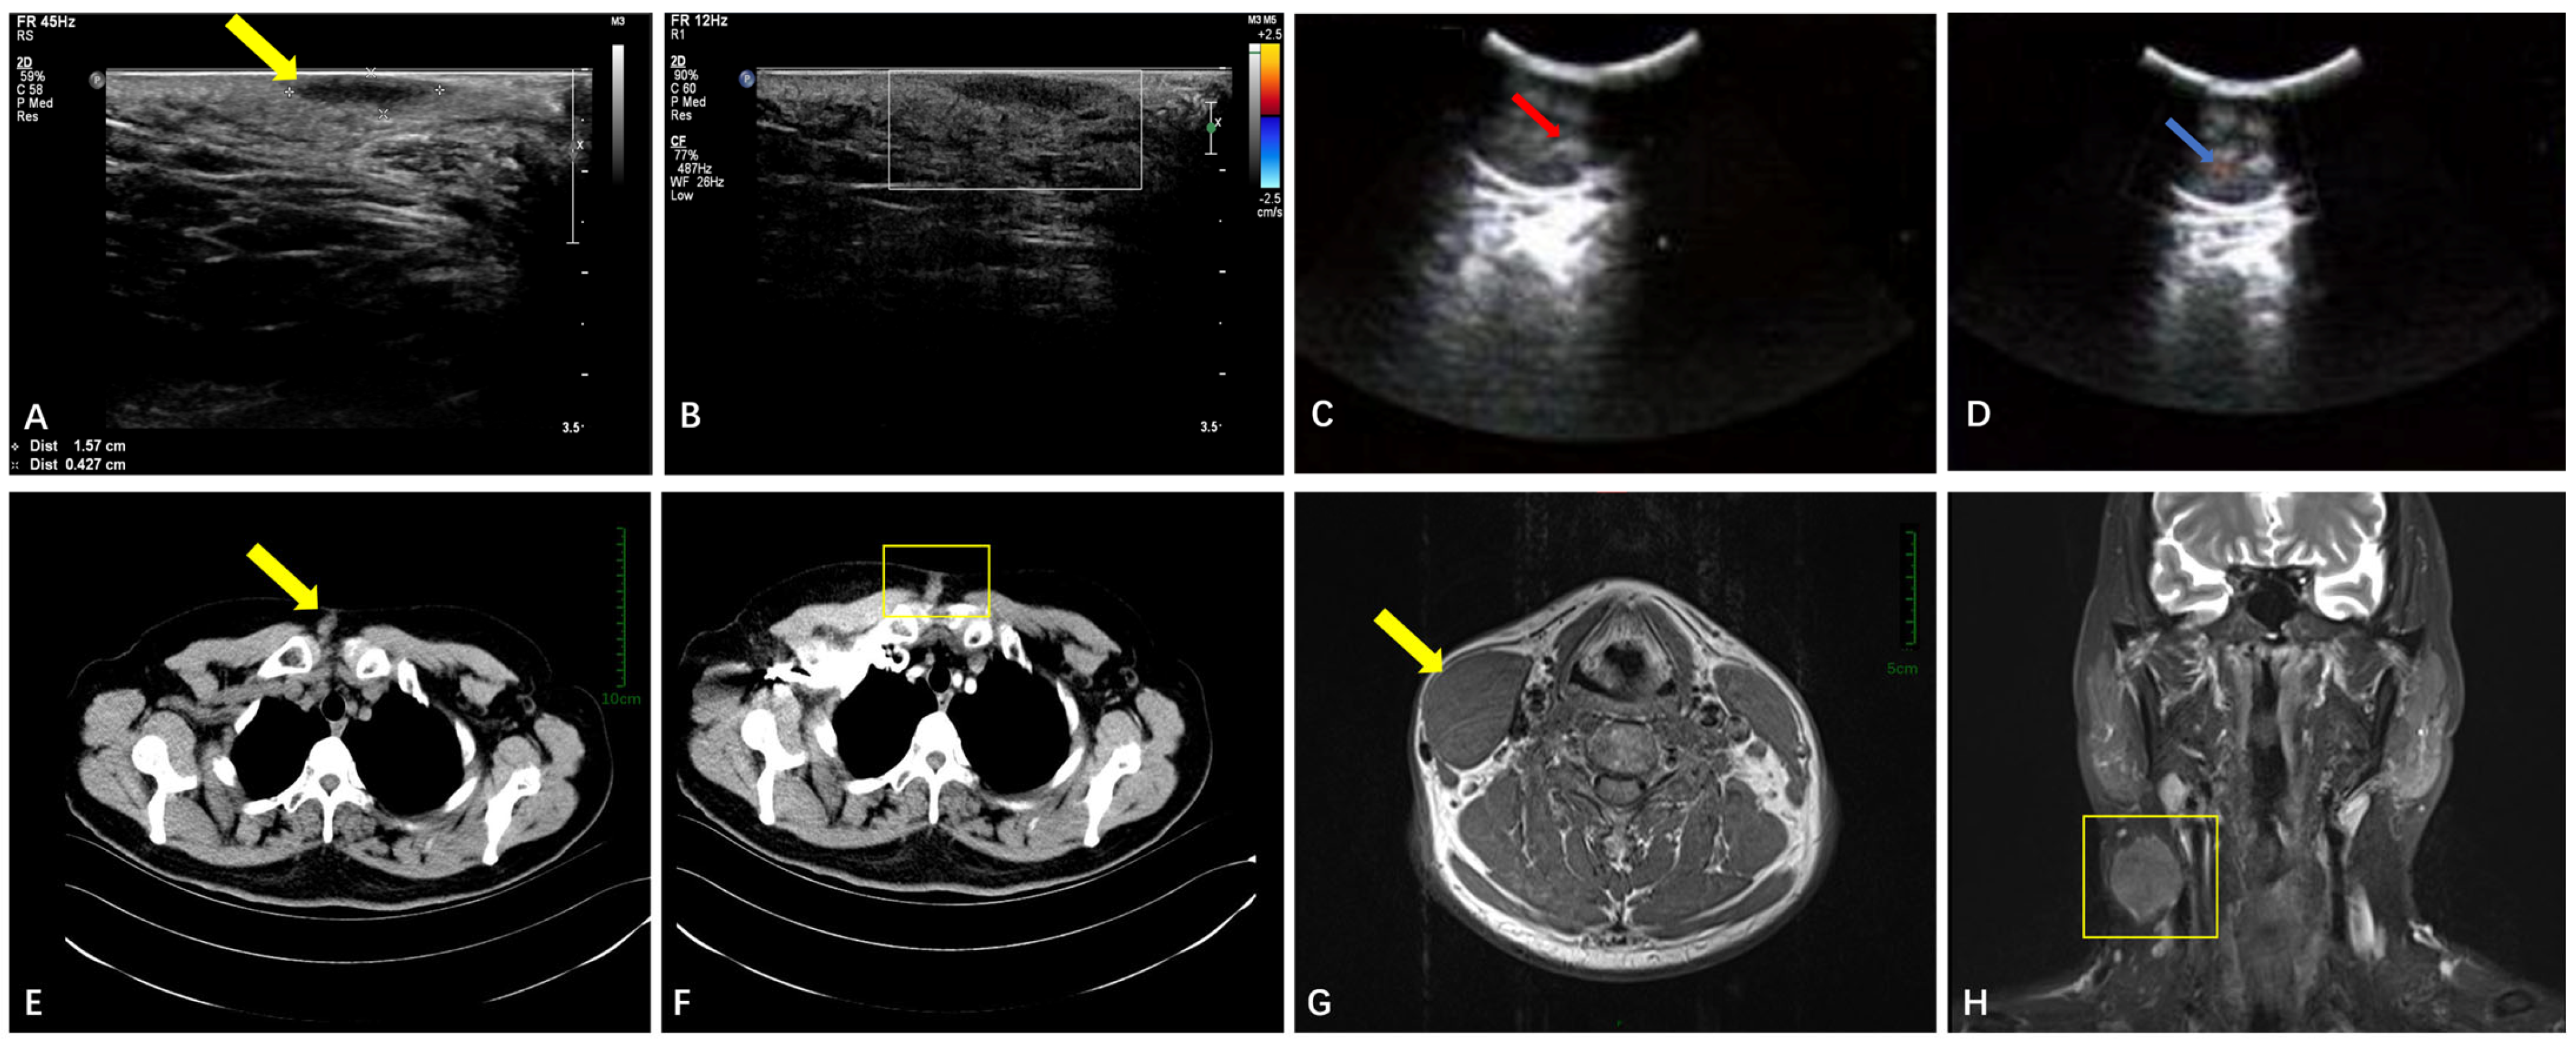

3.2.1. Soft Tissue

| Soft Tissue | Ultrasound (n = 26) | Well-circumscribed hypoechoic masses (n = 25, 96.1%); sparse blood flow. | Larger size (mean: 93 mm); rare irregular margins. |

| CT (n = 9) | Well-defined hypodense nodules (n = 9, 100%); moderate enhancement | N/A | |

| MRI (n = 4) | T1-hypointense (n = 3, 75%) or T1-isointense (n = 1, 25%); variable T2-signals (hyper-/mixed). | N/A (all benign) | |